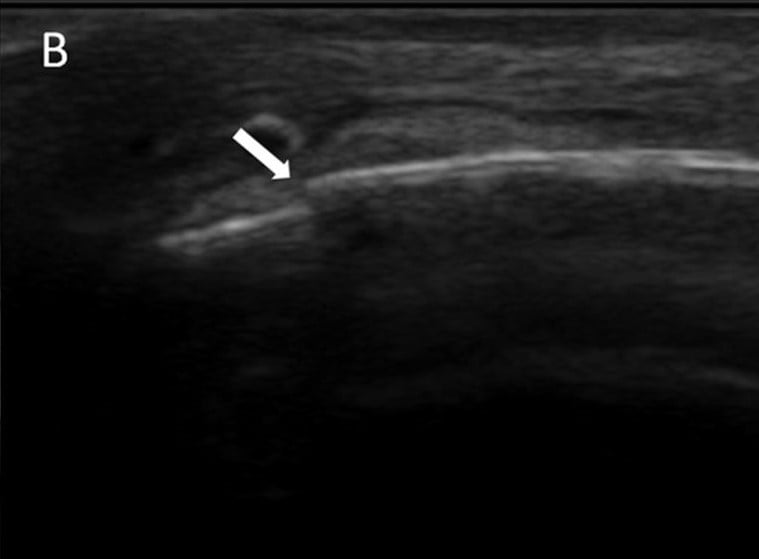

boks esnasında çoğunlukla yumruğunu gevşek tutması sonucu oluşan kırıktır.

4. ve 5. metakarp ( son iki parmak) boyun kırığıdır.

anın sıcaklığı ile hissedilmeyen fakat sonrasında şişerek kendini belli eden acemi işi kırıktır.